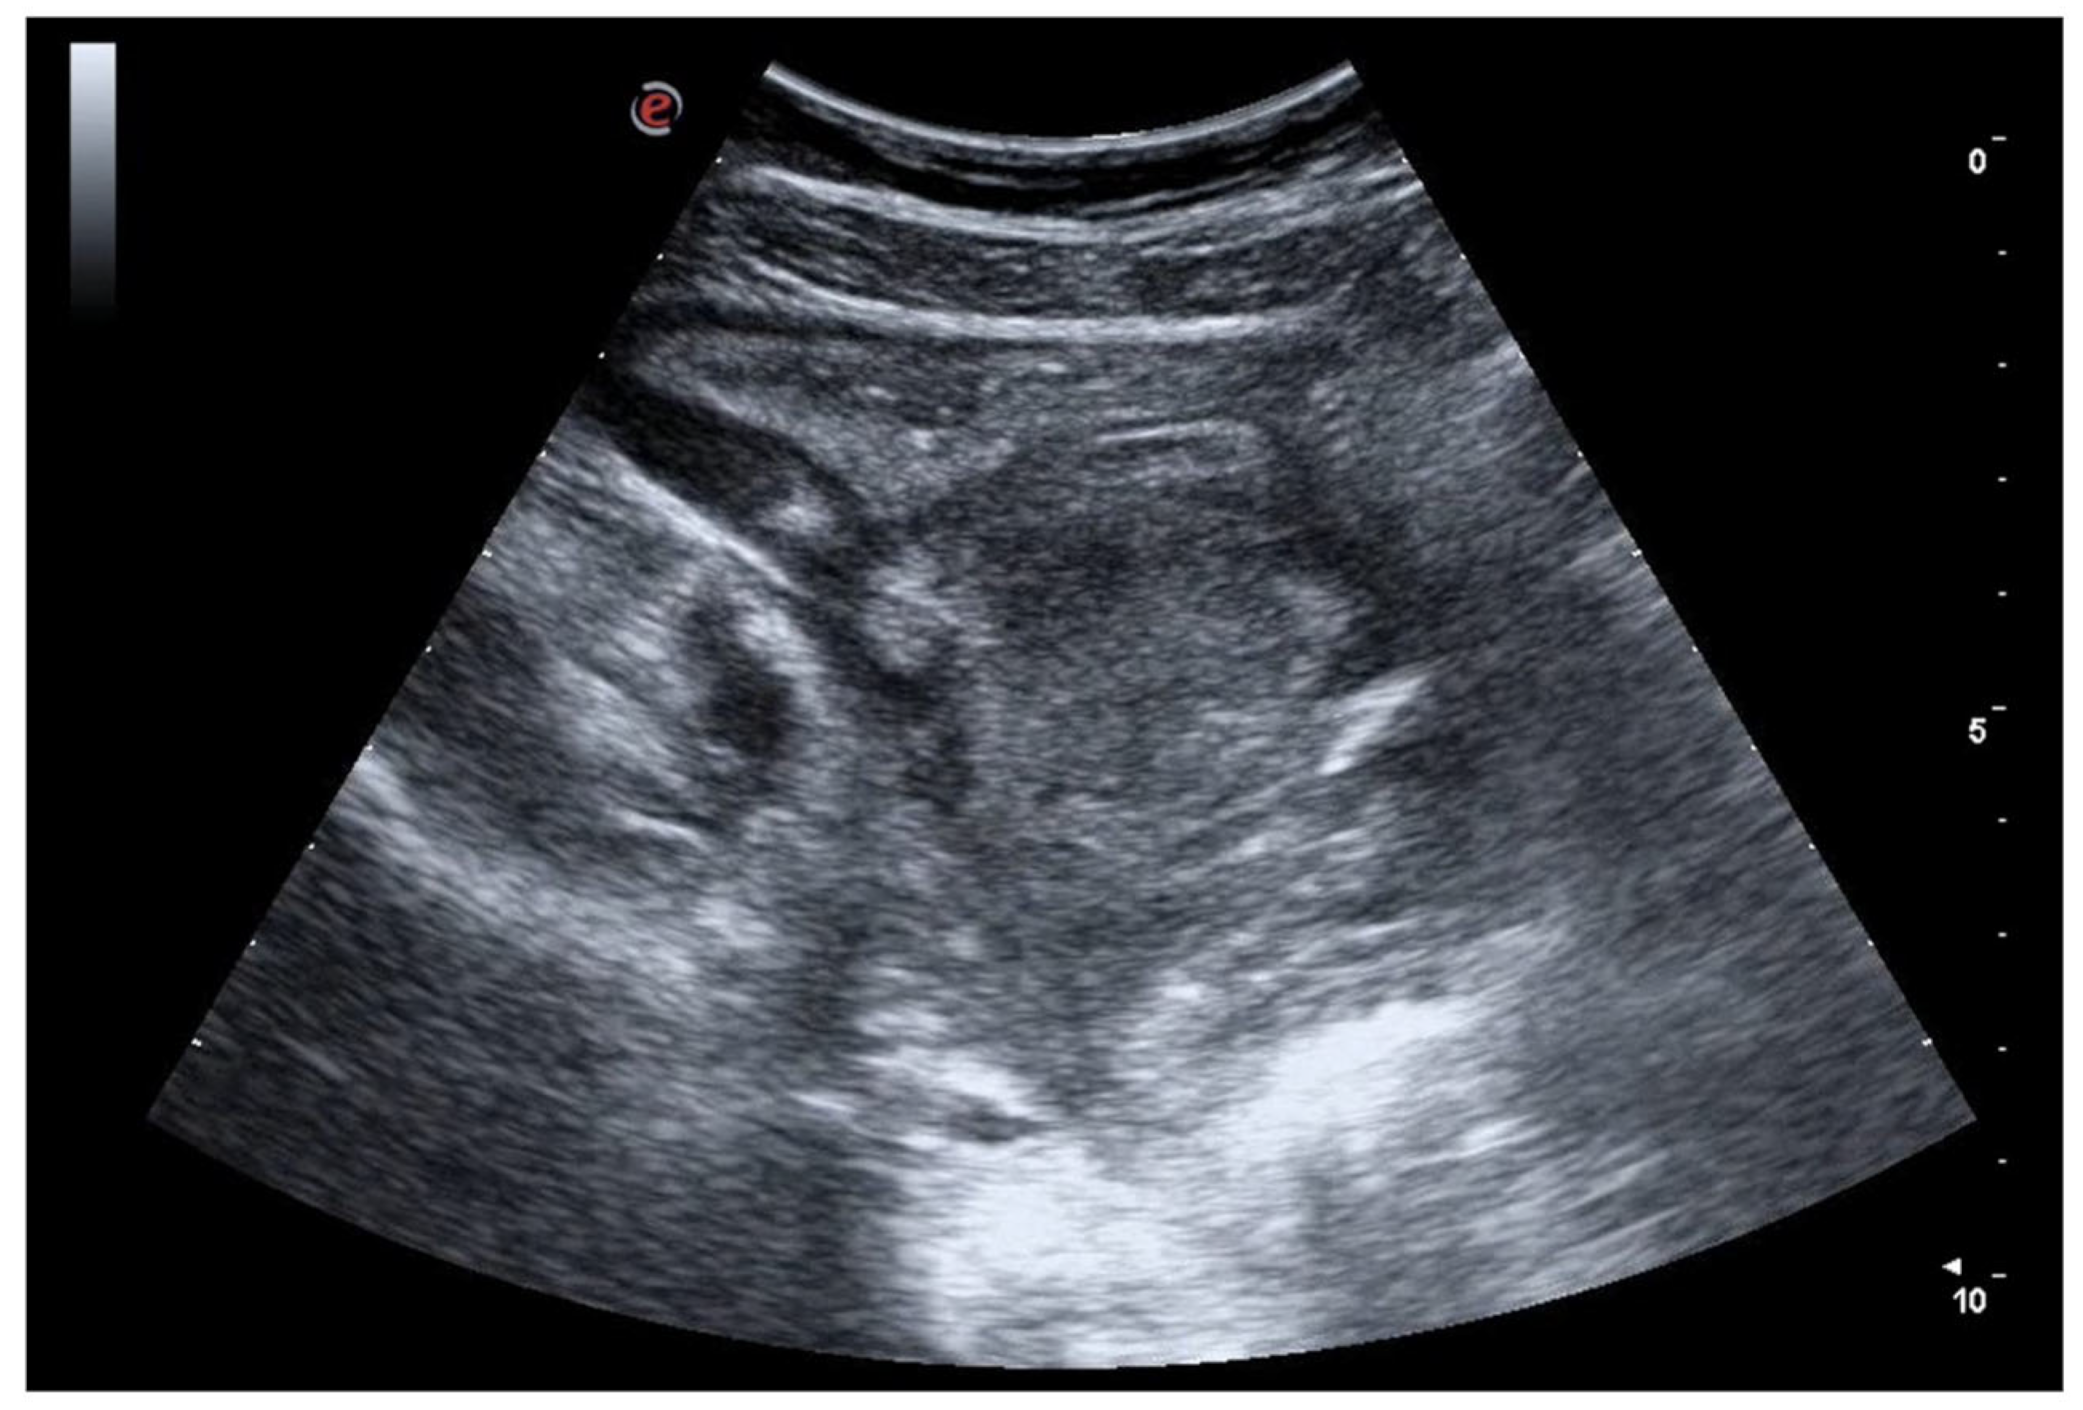

6. Bowel Obstruction

6.1. GIUS Signs of SBO

6.2. GIUS Signs of LBO